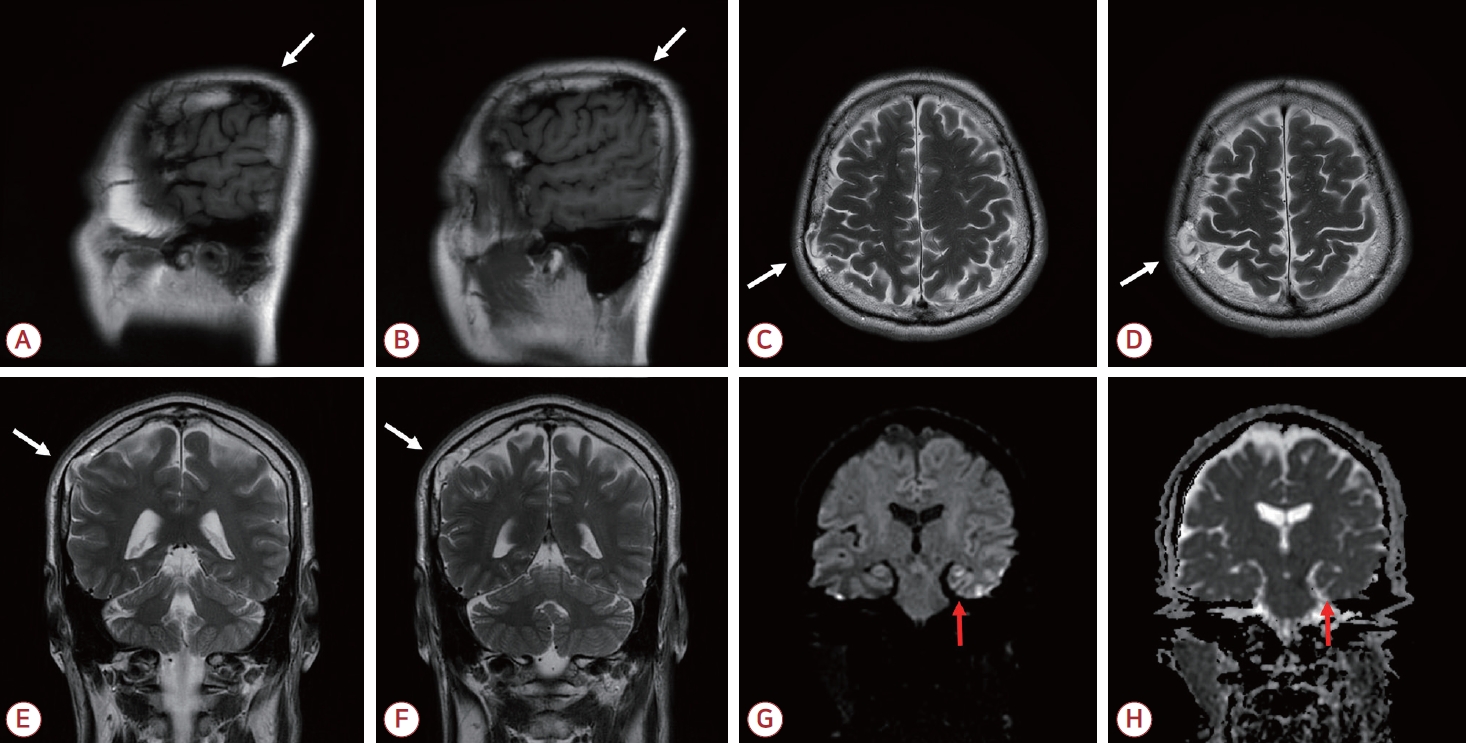

61세 남자가 일주일 전 발생한 5시간 동안의 기억상실로 내원하였다. 동반 증상 및 두부 외상 병력은 없었고 신경계 진찰, 간이정신상태 검사, 뇌파 검사에서 이상은 없었다. 뇌자기공명영상에서 정상 뇌와 등신호를 보이고 우측 두정엽과 연속성을 갖는 조직이 뇌척수액 영역과 함께 두개판내(intradiploic) 공간에 위치해 있었으며 우측 두정골의 결손이 관찰되었다. 확산강조영상에서는 좌측 해마에 점상 고신호강도 병변이 확인되었다(Fig.).

두개판내(intradiploic) 수막뇌탈출증은 두개골의 경막과 내판만 결손되고 외판은 보존되어 뇌조직이 두 판 사이의 공간으로 탈출한 것을 말한다[3]. 이 경우 무증상인 경우가 많아 대부분 우연히 발견되나 발작, 감각 저하, 편마비, 두통 등의 증상을 동반하기도 한다. 현재 널리 받아들여지는 병인은 둔상으로 골절된 내판이 수축하며 발생한 음압에 의하여 뇌조직과 뇌척수액이 두 판 사이 공간으로 탈출한다는 것이다[1]. 외판이 보존된 본 증례 환자의 병변은 모종의 경미한 외상 후 발생한 후천성 병변일 것으로 사료된다. 일과성전체기억상실은 해마의 일시적 기능 저하가, 수막뇌탈출증에서 보고된 증상은 탈출된 뇌조직이 담당하는 기능 이상이 주요 병태생리이므로 두 질환의 상호 연관성은 낮을 것으로 판단하였다.